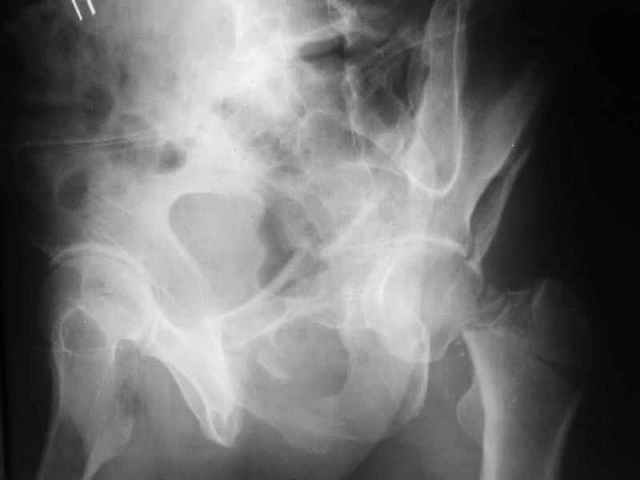

Больной 18 мая 2003 года в автоаварии получил перелом левой вертлужной впадины, вывих бедра. Госпитализирован в один из стационаров области.Вывих вправлен. В последствии бедро вывихивалось еще дважды. На консультацию был представлен снимок от 19.05.03г., больной переведен к нам 3.06.03г. Снимок при поступлении - перелом впадины, задне-верхний вывих бедра. 05.06.2003 г. выполнено открытое вправление вывиха левого бедра и остеосинтез стенки вертлужной впадины двумя винтами. Послеоперационный период без осложнений. Объем движений в левом тазобедренном суставе восстановился полностью. Выписан на амбулаторное лечение в удовлетворительном состоянии с рекомендациями 3 месяца ходить на костылях без нагрузки на оперированную конечность. На контрольных рентгенограммах левого тазобедренного сустава 13.10.2003 г. - признаки консолидации перелома; плотность, форма головки и состояние суставных поверхностей удовлетворительные. Разрешена дозированная осевая нагрузка, на конечность с использованием дополнительной опоры. 19.12.2003 г. больной обратился с жалобами на боли в левом тазобедренном суставе. На рентгенограммах левого тазобедренного сустава 19.12.2003 г., 20.02.04г. - асептичекий некроз головки бедра. 5.04.04г. - эндопротез. Сейчас ходит без трости, не хромает. Особенность эндопротезирования - при удалении винтов прослежена линия перелома заднего края впадины и предложено установить чашку несколько меньшего диаметра, чтобы она была покрыта несломанной частью.

Случай, представленный Вами, совсем не идентичен обсуждаемому. У Вашего пациента был поперечный перелом с переломом заднего края, а в обсуждаемом случае - высокий двухколонный перелом вертлужной впадины.

То есть в представленном Вами случае был перелом заднего типа, в нашем случае центрального. У Вашего больного был застарелый задний вывих, у нашего - перелом шейки. Столь раннее разрушение головки, вероятно, было во многом обусловлено тем, что не была достигнута анатомическая репозиция, головка бедра осталась смещенной кзади, что является частой ошибкой при крупных фрагментах свода.

Необходимость фиксации вертлужной впадины в нашем случае вообще под вопросом, так как конгруэнтность сохранена (вторичная конгруэнтность типична для двухколонных переломов).